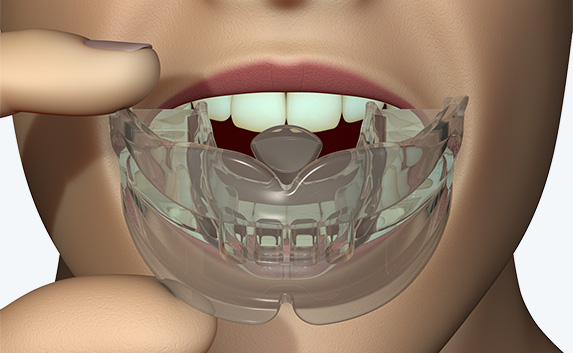

The Myosa®for TMJBDS®S1 is used in patients with a Breath Hold Time (BHT) of 20 seconds or more. It works by advancing the sleeper’s lower jaw and opening the bite, which has the effect of opening the airway. Additionally, the S1 has four breathing holes at the front to regulate breathing. For better retention during sleep, the patient can use the mouldable version of the S1 appliance (S1M). Progress to the S2 when the patient’s BHT reaches 35 seconds or more.